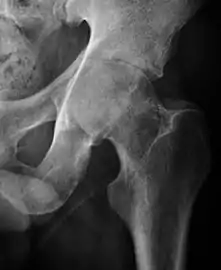

Projectional radiography ("X-ray") is the first imaging technique of choice in hip pain, not only in older people with suspected osteoarthritis but also in young people without any such suspicion. In this case plain radiography allows categorization as normal hip or dysplastic hip, or with impingement signs, pincer, cam, or a combination of both.[1]

Projectional radiography ("X-ray") is currently useful not only in older people in whom osteoarthritis of the hip is suspected but also in younger people without osteoarthritis, who are being evaluated for femoroacetabular impingement (FAI) or hip dysplasia.[1]

Plain radiography allows us to categorize the hip as normal or dysplastic or with impingement signs (pincer, cam, or a combination of both). Besides these, pathologic processes like osteoarthritis, inflammatory diseases, infection, or tumors can also be identified (Figure 1).[1]

- Osteoarthritis

In adults, one of the main indications for radiographs is the detection of osteoarthritic changes (Figure 1(e)). Nevertheless, radiographs usually detect advanced osteoarthritis that can be graded according to the Tönnis classifications. The grading system ranges from 0 to 3, where 0 shows no sign of osteoarthritis. Intermediate grade 1 shows mild sclerosis of the head and acetabulum, slight joint space narrowing, and marginal osteophyte lipping. Grade 2 presents with small cysts in the femoral head or acetabulum, moderate joint space narrowing, and moderate loss of sphericity of the femoral head. Grade 3 is the severest form of osteoarthritis, which manifests as severe narrowing of the joint space, large subchondral cyst with productive bone changes that may lead to deformity of the bone components of the joint, while secondary osteoarthritis due to calcium pyrophosphate deposition can be diagnosed when calcification of hyaline cartilage and fibrocartilage is detected.[1]